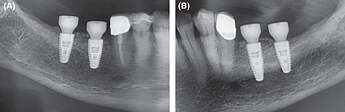

Figure 7.

Extracts from postoperative OPG after implantation and GBR in the third and fourth quadrant. A, fourth quadrant. B, third quadrant

Figure 10.

Extracts from postoperative OPG: Gingival former in the third and fourth quadrants in situ. A, Allogeneic site showing good integration of the implants and no loss of crestal bone. Relining layer of DBBM particles in situ. B, Same situation on the autologous site showing similar results compared to the allogeneic site

Figure 12.

Extracts from OPG: Radiological situation after prosthetic treatment. A, Allogeneic site with good integration of the implants and no crestal bone loss and well‐integrated relining layer. B, Autologous site showing good integration, no bone loss and well‐integrated relining layer on the autologous site